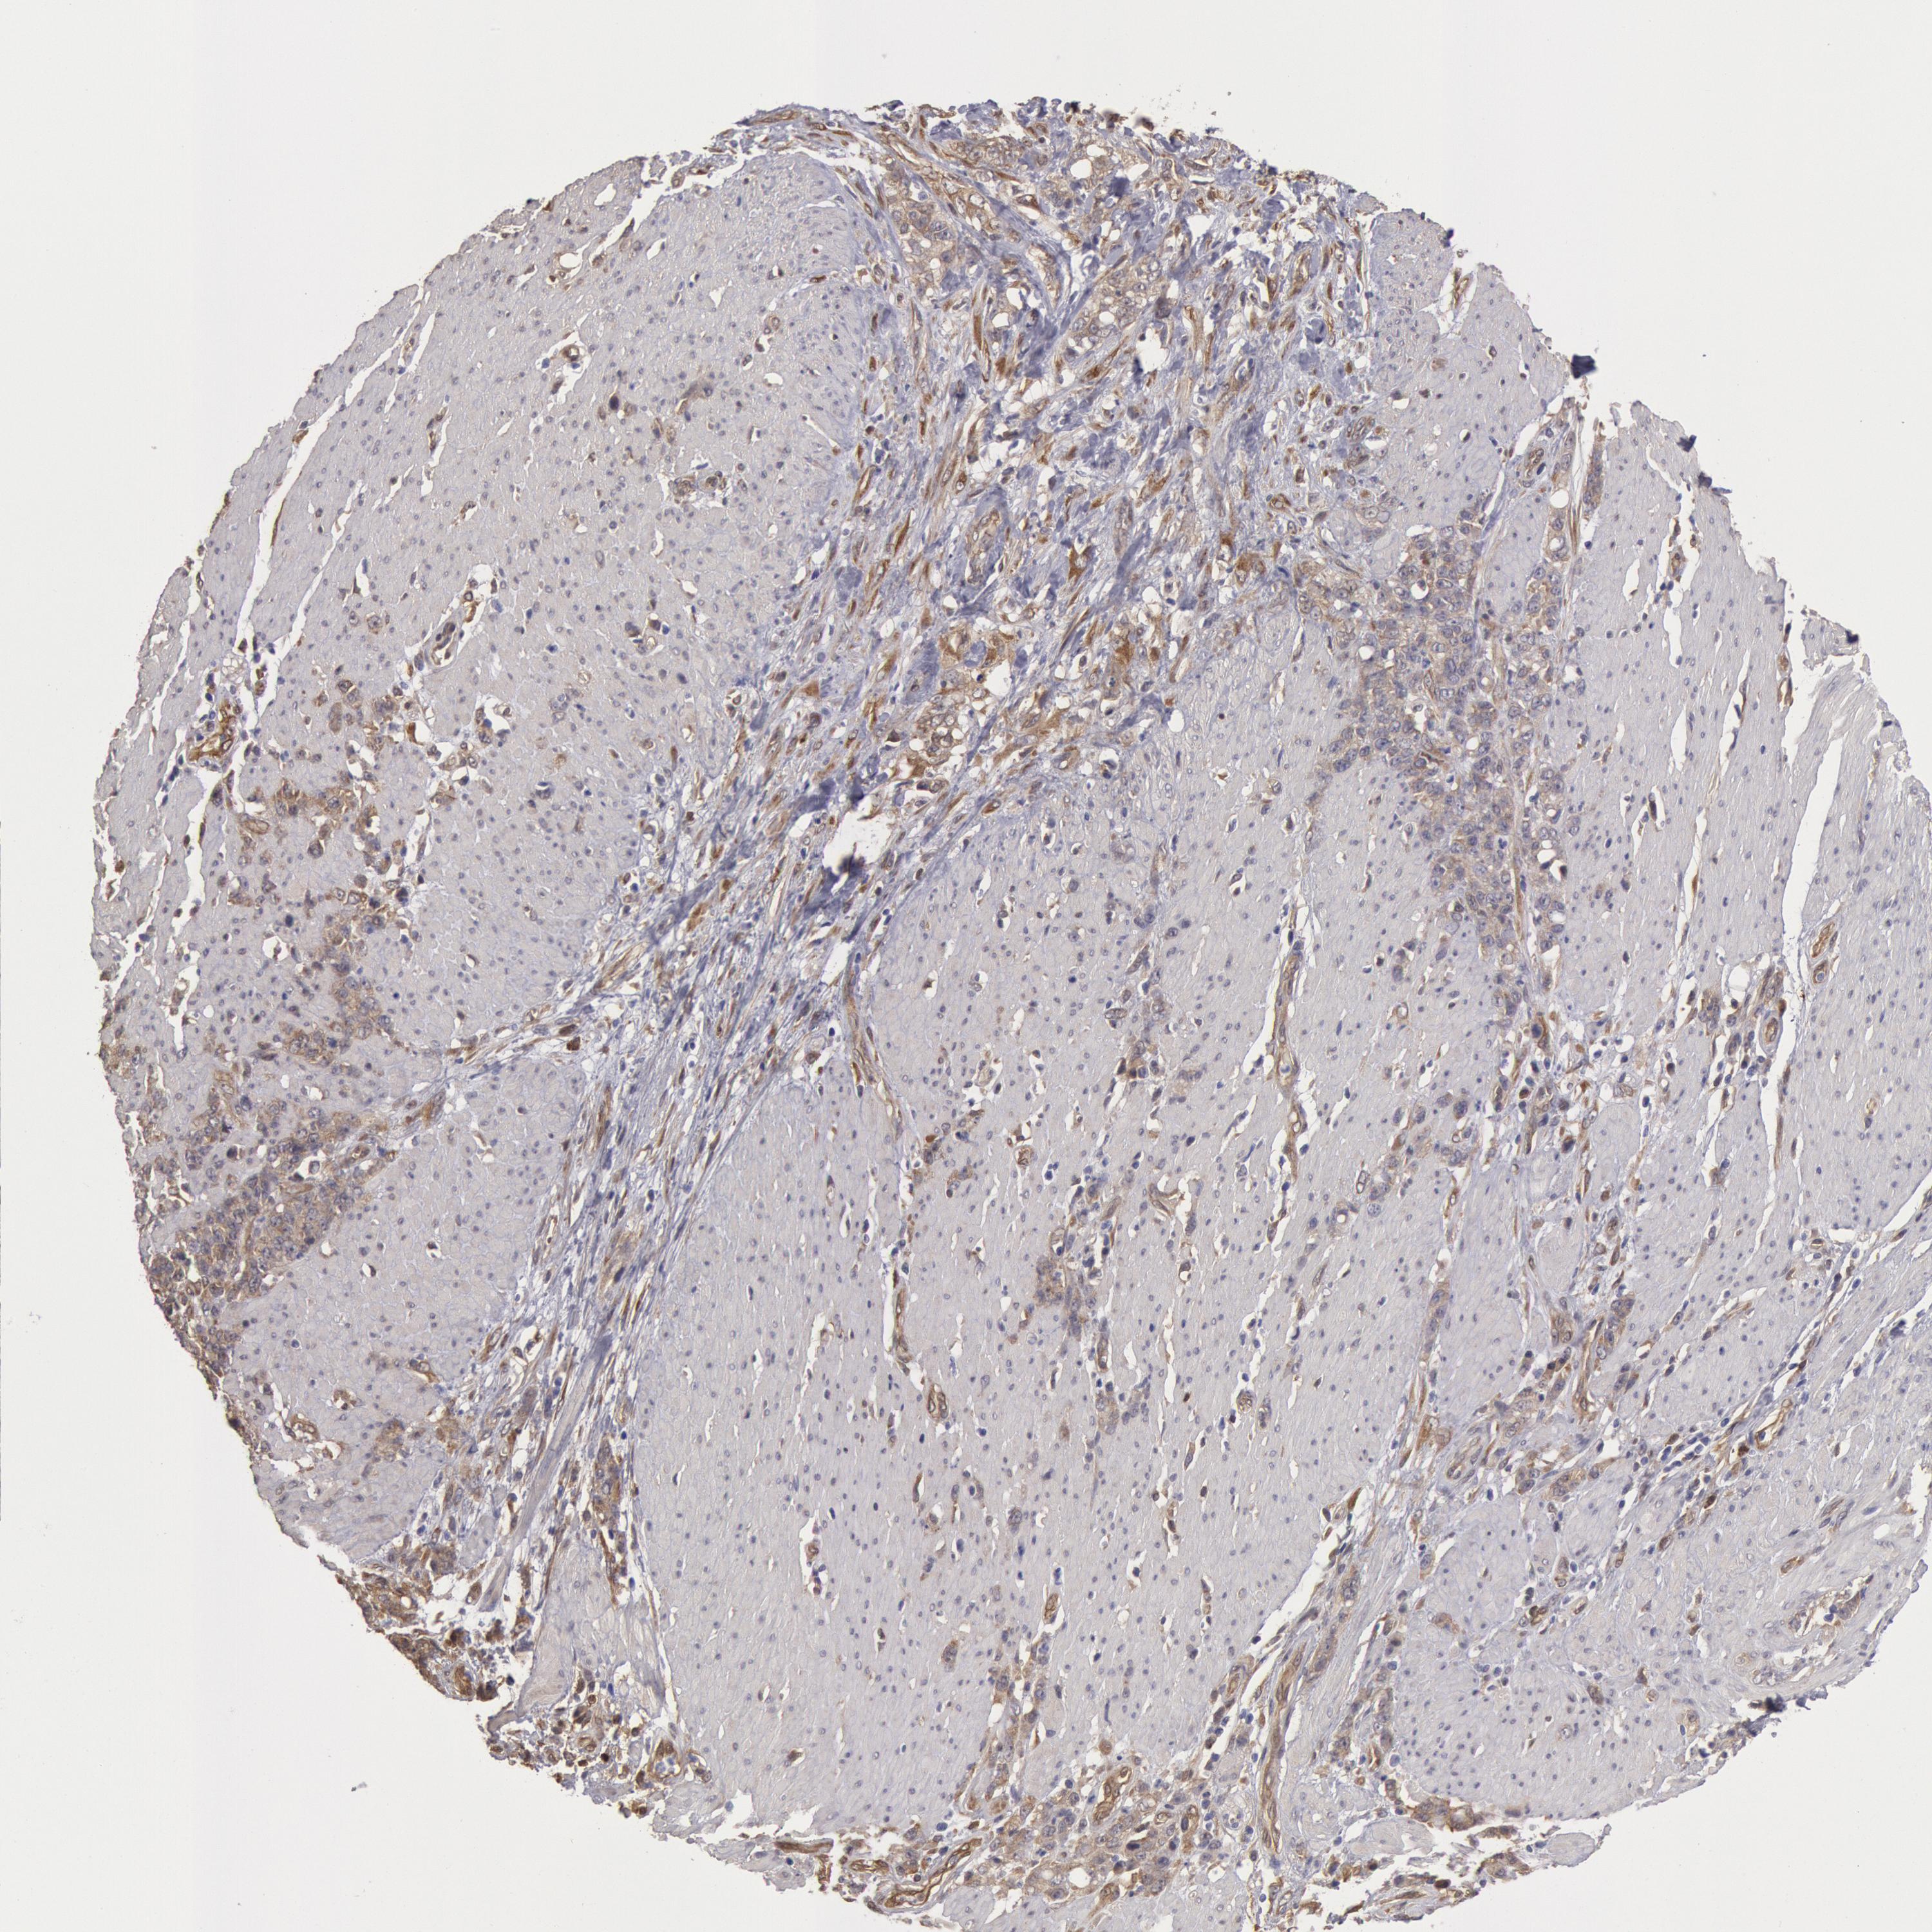

STOMACH CANCER - Protein expressioni

A mouse-over function shows sample information and annotation data. Click on an image to view it in a full screen mode. Samples can be filtered based on level of antibody staining by selecting one or several of the following categories: high, medium, low and not detected. The assay and annotation is described here.

Antibody stainingi

Antibody staining in the annotated cell types in the current human tissue is reported as not detected, low, medium, or high, based on conventional immunohistochemistry profiling in selected tissues. This score is based on the combination of the staining intensity and fraction of stained cells.

Each image is clickable and will lead to virtual microscopy that enables deeper exploration of all samples and also displays staining intensity scores, fraction scores and subcellular localization as well as patient and tissue information for each sample.

Antibody HPA001336

Staining

High

Medium

Low

Not detected

Intensity

Strong

Moderate

Weak

Negative

Quantity

>75%

75%-25%

<25%

None

Location

Nuclear

Cytoplasmic/membranous

Cytoplasmic/membranous,nuclear

Adenocarcinoma, NOS